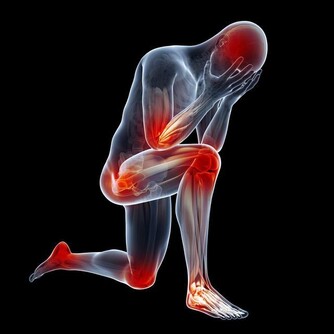

3.多汗疼痛→ 心臟病這是由於心臟的血液供應不足而使心肌受到損傷而引起的。

它的表現包括:胸部的疼痛或壓迫感,會持續數分鐘。

疼痛有時也會放射到你的肩膀、手臂或背部。此外,還會有呼吸困難和大量出汗的情況。

如果你或你的親人出現了這樣的症狀,應該立即到醫院就診。

時間就是生命,每一分鐘都很重要!